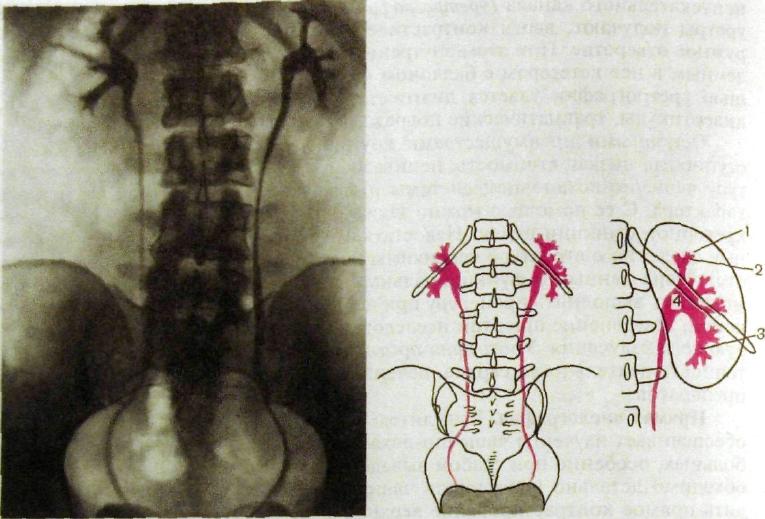

Экскреторная урография при нефроптозе: диагностические изображения